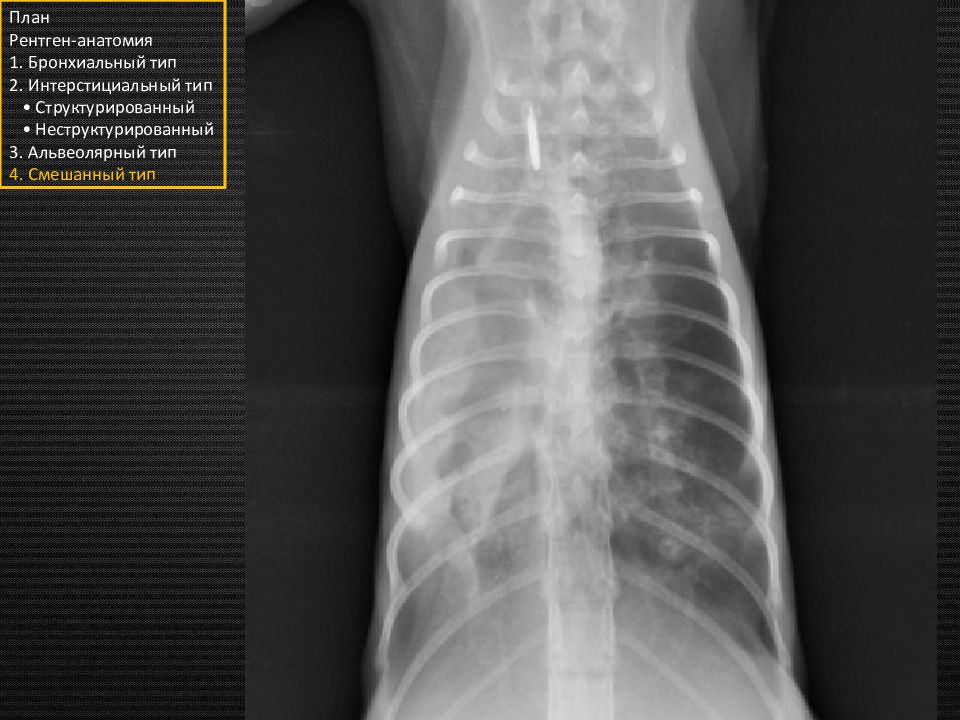

Прямая проекция План Рентген-анатомия 1. Бронхиальный тип 2. Интерстициальный тип • Структурированный • Неструктурированный 3. Альвеолярный тип 4. Смешанный тип